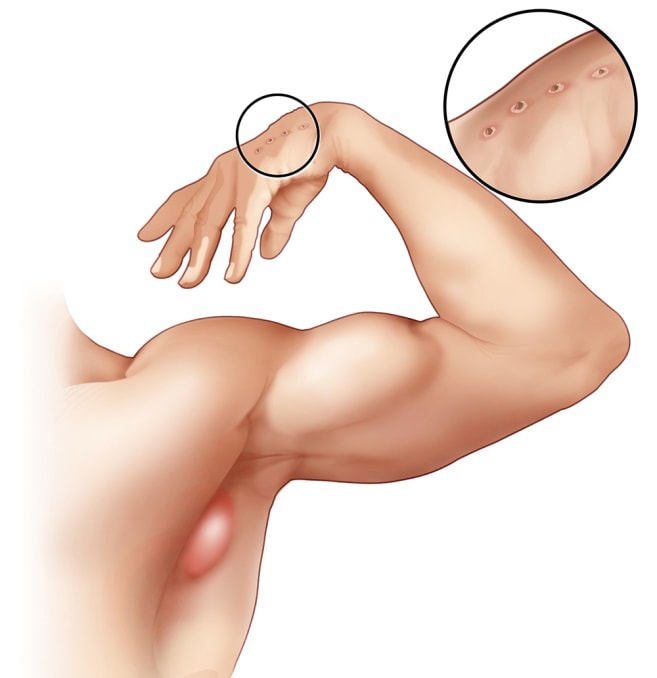

Cat Scratch Disease | Causes, Symptoms  What You Should Do for a Cat Bite or

Cat scratch fever: Causes, symptoms  Dealing with Cat Scratch Disease

Dealing with Cat Scratch Disease  A Review on Cat Scratch Disease and it

Cat Scratch Disease (Cat Scratch Fever  Cat Scratch Disease | Healthy Pets

PCR of Cat scratch disease  Cat Scratch Disease (Cat Scratch Fever

Cat-scratch disease | Radiology  Cat Scratch Disease and Your Child

Cat Scratch Disease and Your Child PDF) Cat-scratch disease: A wide